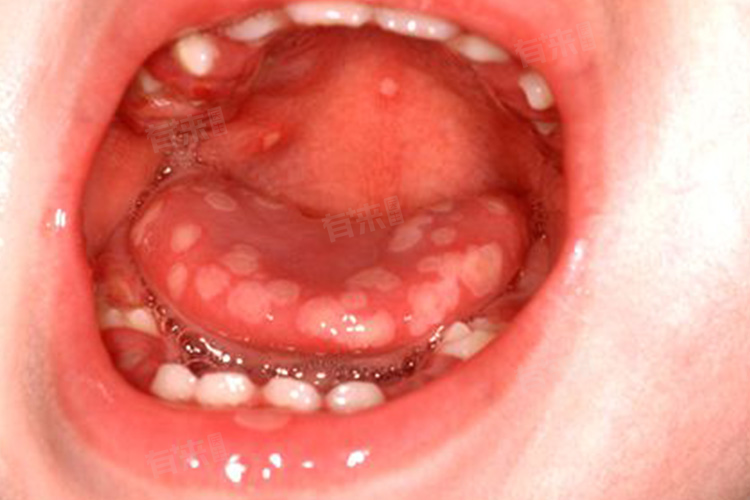

2、舌头白斑:艾滋病患者的舌头上可能出现白色斑点或斑块,这些白斑可能是由白念珠菌感染引起,这些白斑通常出现在舌背、舌缘等部位,且不易擦去,如果舌头上出现持续不退的白色斑点或斑块,且伴随有疼痛或不适感,应尽快就医检查。

3、毛状白斑:毛状白斑是艾滋病早期的一种特异性临床表现,通常出现在舌头两侧边缘部位,呈白色或灰色,病变可蔓延至舌腹和舌背部,这种白斑不易擦去,且可能伴有轻微疼痛或不适感,毛状白斑的出现,往往提示机体免疫系统已经受到严重损害。

5、舌头溃疡:艾滋病患者的舌头表面可能出现溃疡,这可能是由于病原体感染、营养不良或免疫系统受损等多种因素导致的,溃疡通常伴有疼痛、出血等症状,严重影响患者的生活质量,如果发现舌头上出现溃疡,且持续不退,应尽快就医检查。